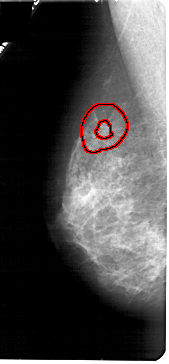

A_1790_1.LEFT_CC

LEFT_CC LINES 5281 PIXELS_PER_LINE 2281 BITS_PER_PIXEL 12 RESOLUTION 43.5 OVERLAY

FILE: A_1790_1.LEFT_CC.OVERLAY

TOTAL_ABNORMALITIES 1

ABNORMALITY 1

LESION_TYPE MASS SHAPE IRREGULAR MARGINS SPICULATED

ASSESSMENT 4

SUBTLETY 1

PATHOLOGY MALIGNANT

TOTAL_OUTLINES 2

BOUNDARY

CORE